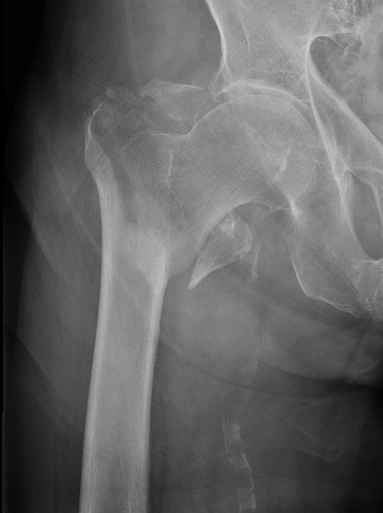

Definition

Fracture which extends between the trochanters of the proximal femur

Extra capsular / well vascularized

Evans Classification

Two main types

- Type 1 Intertrochanteric

- Type 2 Reverse Oblique

Type 1 Intertrochanteric

2 part undisplaced

2 part displaced

3 part without posterolateral support (GT fracture)

3 part without posteromedial support (LT fracture)

4 part without posterolateral or posteromedial support

Type II Reverse Oblique Type

Inherently unstable - tendency of femoral shaft fragment to shift medially

Reverse oblique fractures